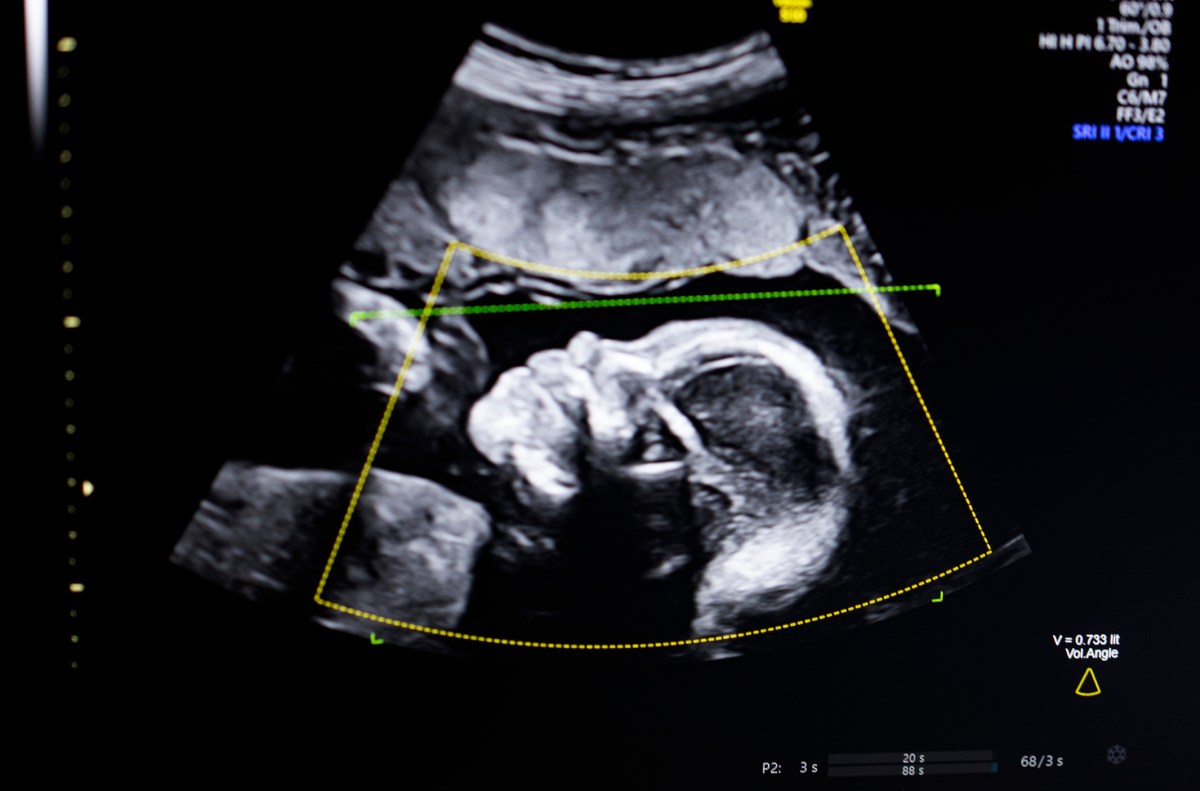

TechCrunch hack The winner of the Battle of 2023, BioticsAIannounced on Monday that it has received FDA approval for its AI software which helps detect fetal abnormalities in ultrasound images.

The technology uses computer vision AI to “support fetal ultrasound quality assessment, anatomical fit, predictive reporting, and seamless integration into clinical workflow,” Bustami told TechCrunch.

Bustami said that prenatal ultrasound has become the “cornerstone” of pregnancy monitoring, but its low-quality images can lead to wrong diagnoses.